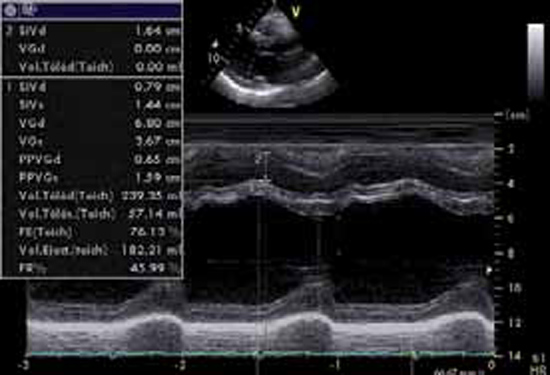

Figure 3 : VG dilaté en écho-TM

Le diamètre télédiastolique du VG atteint 68 mm, le diamètre télésystolique demeure normal à 36,7 mm. La fonction systolique est normale, avec un pourcentage de raccourcissement de 46 % et une fraction d’éjection (FE) de 76 %.